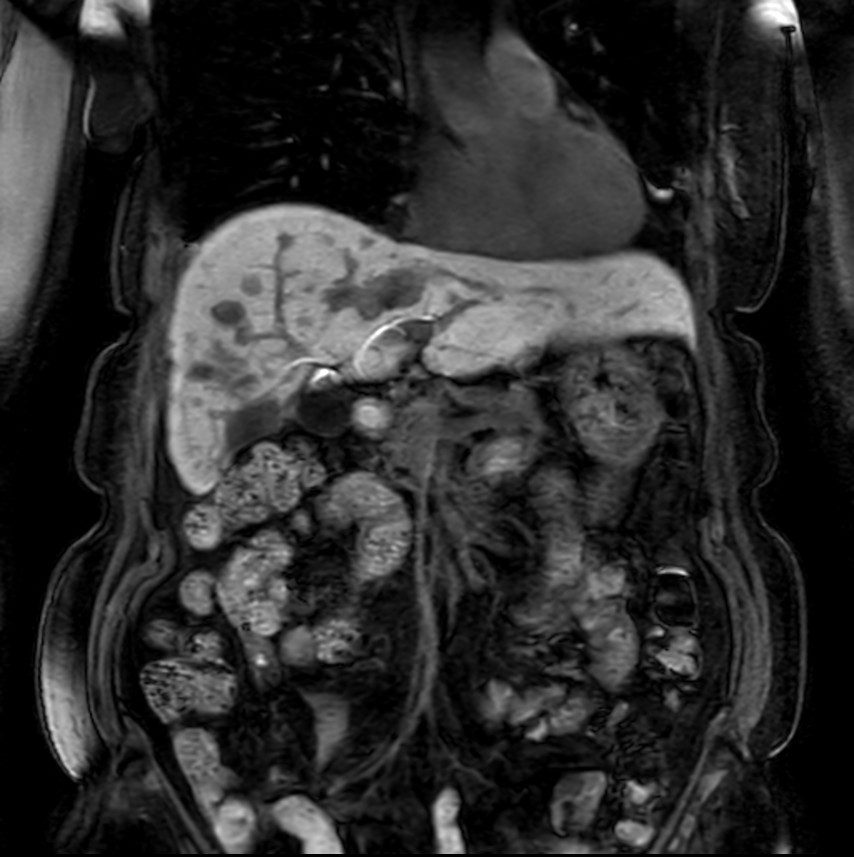

Coronal MRCP SSh